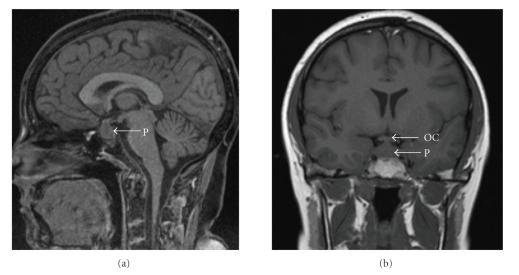

Wegener's granulomatosis of the pituitary gland resulting in diabetes insipidus is a rare complication of the disease. Standard treatment for Wegener's granulomatosis involves a combination of prednisolone and cylophosphamide, however biologic agents are now being used in refractory cases. We report three cases of patients with diabetes insipidus as a complication of Wegener's granulomatosis who were treated with biologic agents. All three cases showed clinical response to treatment with biologic agents including rituximab and alemtuzumab and two cases demonstrated improvement in pituitary gland abnormalities by MRI. Clinicians should be aware that diabetes insipidus can present as a complication of Wegener's granulomatosis and that biologic therapies may be effective in refractory cases.